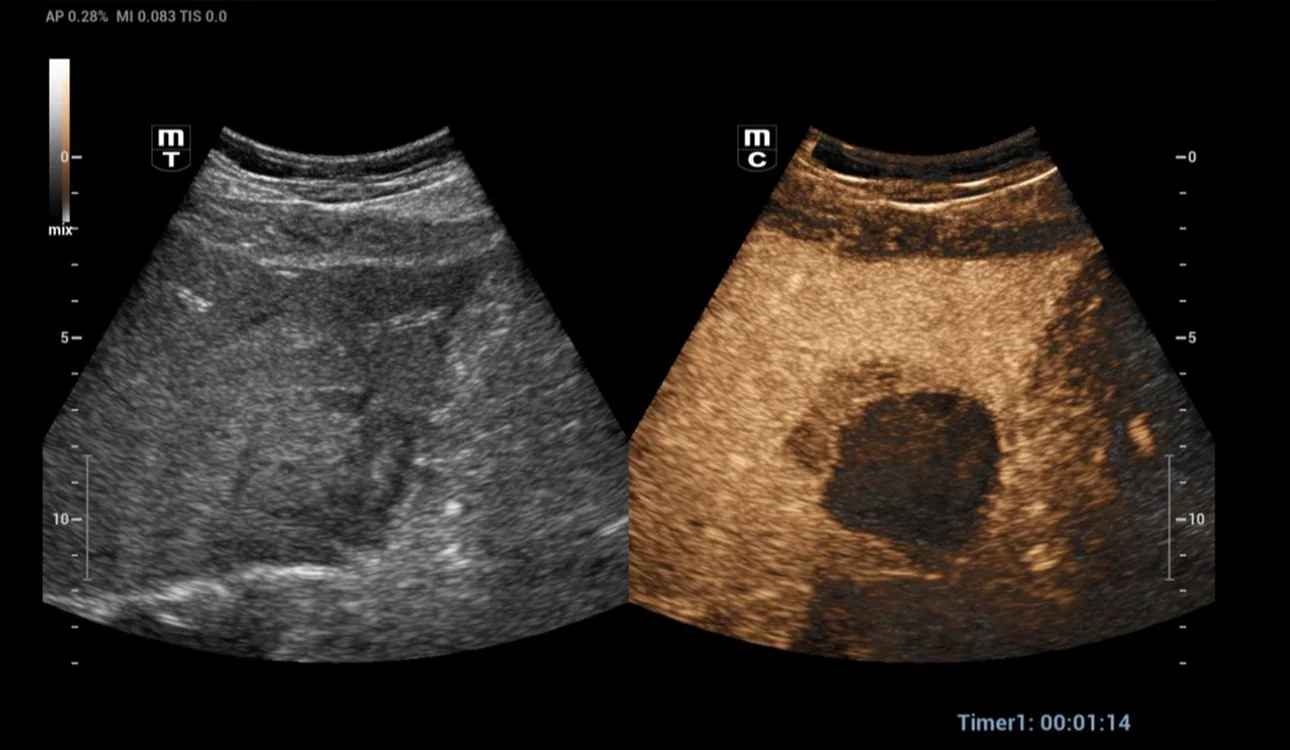

After a month, a CEUS exam was performed to assess the post-thermal ablation zone. The post-thermal ablation zone in the arterial phase after injection of 1.2 ml of Sonovue intravenously (Fig 2). A clear margin of necrosis developed from post-thermal ablation was visible. The necrotic region didn’t undergo contrast enhancement in any phase of the examination. In the portal phase (Fig 3-4), contrast washout was observed in the liver parenchyma adjacent to the ablation zone (arrows). Then a CT scan was performed to verify the case (Fig 5). A hepatic vein adjacent to the post-thermal ablation recurrence area was visible.

Fig. 4 Mix image of grayscale and contrast-enhanced US (portal phase).